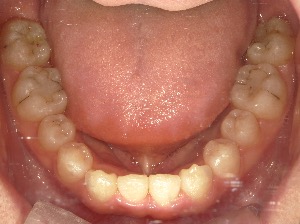

before

患者さんの年齢 30代 男性 症状 ガタガタを治したい 治療内容 ワイヤー矯正治療 費用 88万(税抜) 治療期間・回数 治療期間2年半、通院回数20回 メリット 口元が綺麗 デメリット・リスク 期間がかかることがある 患者さまの声 見た目が良くなった - 矯正治療